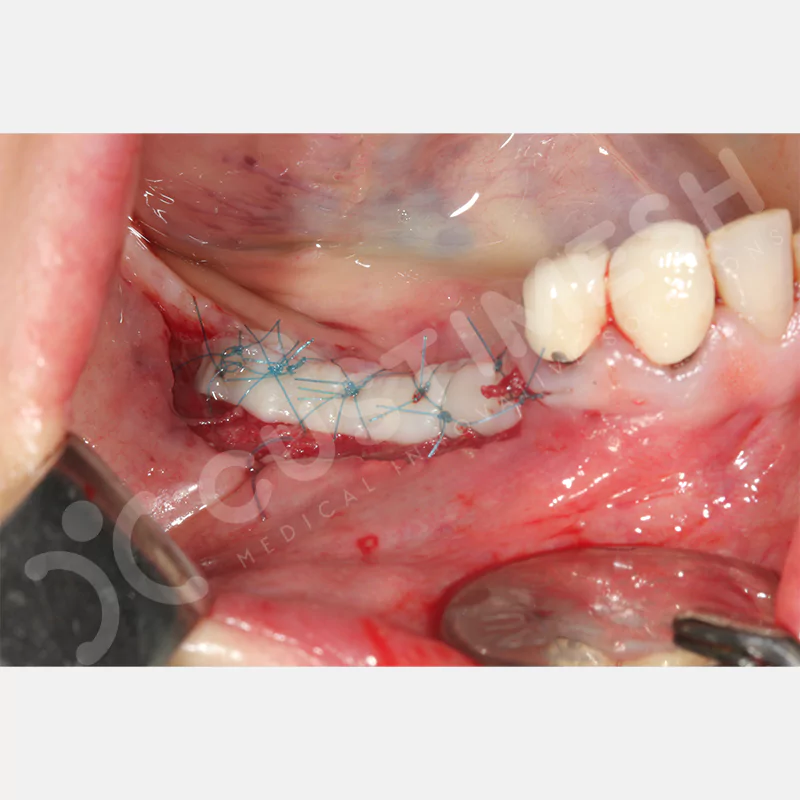

VAKA 1

VAKA 2

VAKA 3